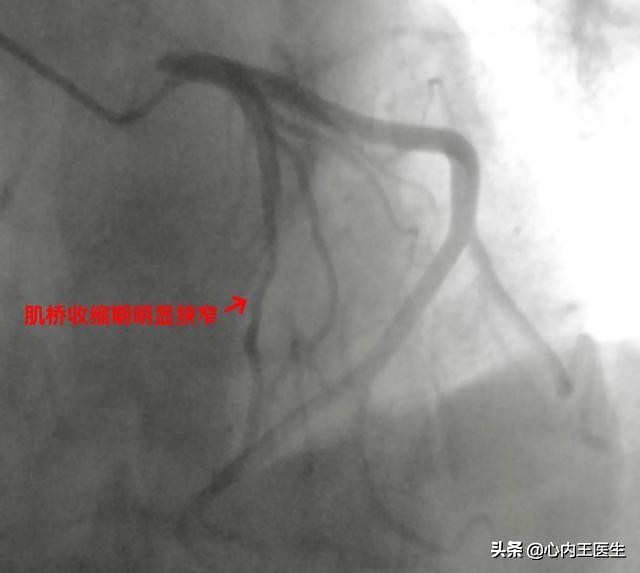

今天上午,这位大爷行冠状动脉造影提示冠状动脉肌桥,这就很明确的排除了冠心病。肌桥一般问题不大,就是血管在部分肌肉的下面穿过,可能活动状态下影响部分血供,心脏肌肉收缩的时候血管被压迫变窄,舒张期狭窄明显解除。